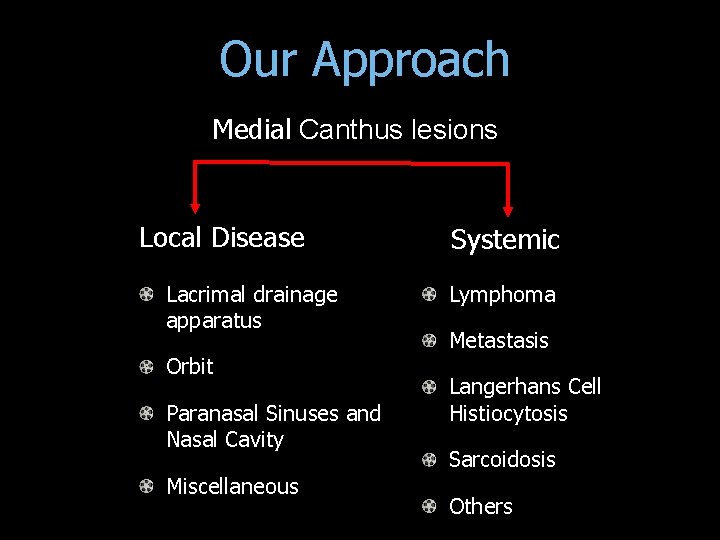

Our Approach Medial Canthus lesions Local Disease Lacrimal drainage apparatus Orbit Paranasal Sinuses and Nasal Cavity Miscellaneous Systemic Lymphoma Metastasis Langerhans Cell Histiocytosis Sarcoidosis Others